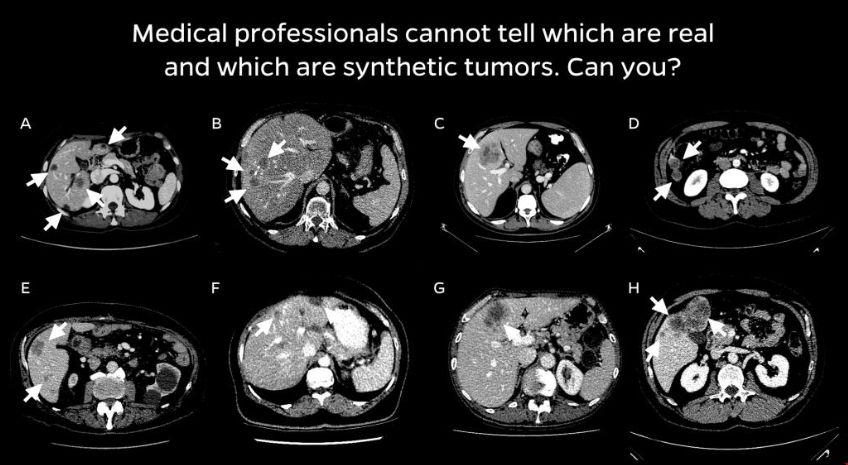

該團隊與放射科醫生合作,設計了一種四步合成現實腫瘤的方法。首先,他們為人造腫瘤選擇了避免與周圍血管碰撞的位置。接下來,他們添加了隨機的“噪聲”模式,這樣他們就可以生成在真實腫瘤上發現的不規則紋理,并生成反映真實腫瘤不同輪廓的形狀。最后,他們模擬了腫瘤擠壓周圍環境的傾向,這改變了它們的外觀。研究人員說,合成的腫瘤是超現實的,并且通過了視覺圖靈測試——也就是說,即使是醫學專業人員在視覺檢查中也會把它們和真實的腫瘤混淆。

然后,該團隊只使用這些合成腫瘤訓練了一個人工智能模型。他們說,由此產生的模型明顯優于之前類似的方法,并且可以達到與在真實腫瘤上訓練的人工智能模型相當的性能。